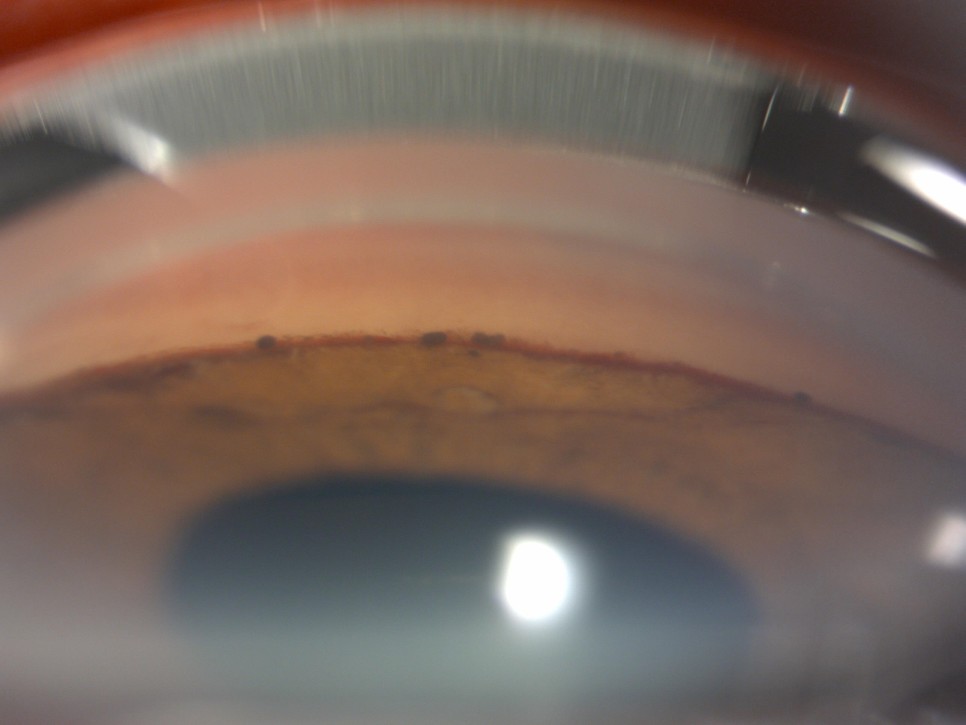

2 . Gonio photography

신생혈관이 방수 유출로인 섬유주를 덮음으로써 발생하는 전방각의 유착을 확인하기 위하여 Goniophotography로 촬영한 사진이다.